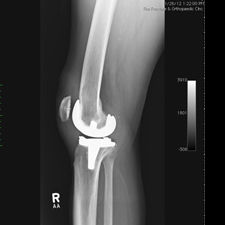

Patient seen with Bilateral Knee Pain and had been unable to walk for two (2) years.

On clinical and radiological examination, he was assessed as having Severe Primary Osteoarthritis of both knees.

Bilateral Total Knee Replacement was recommended, and performed on July 27th 2011. Since surgery, the patient has made good progress and can now mobilize with the aid of a walker.

His x-rays and clinical examination suggest good early outcome with a fully mobilized patient with pain free knees and the ability to walk independently.